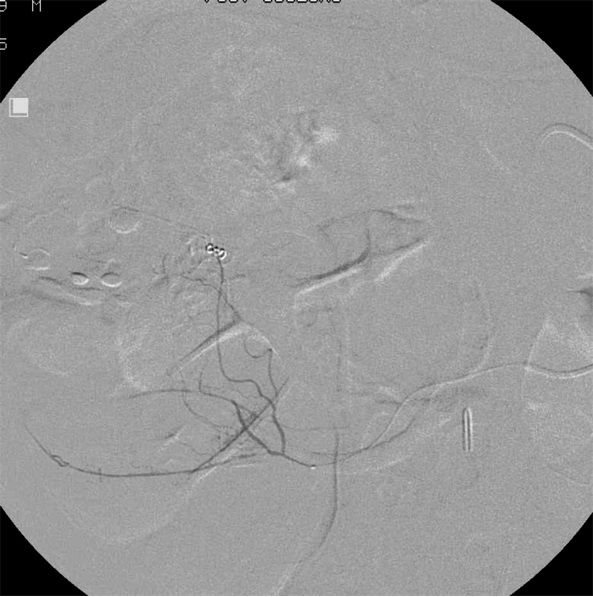

● 结肠梗死20% Colonic infarction in up to 20% of cases ● 技术几乎被放弃 Technique was largely abandoned ● 微导管时代 Microcatheter era ● LGI 栓塞梗死0-1% LGI embo done with infarction rates 0-1% ●下消化道出血微导管栓塞成为一线治疗 Microcatheter techniques have allowed embo to become a first line therapy 下消化道出血栓塞共轴导管选择使导管到达终末支的位置更满意 病例1

病例2